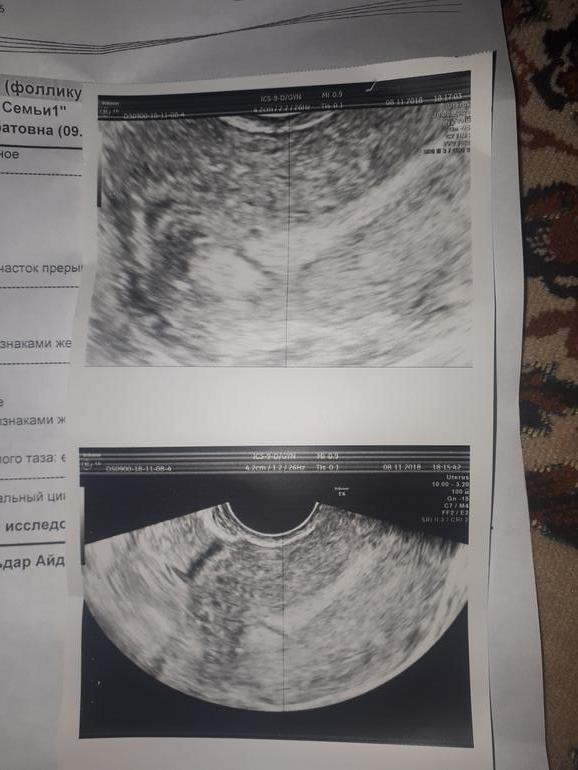

Фолликулометрияне выдержала , тем более вчера сильно колол левый яичник, очень тянул, сходила сейчас на узи. Овуляция была и в правом и в левом, двойная )))) что очень радует ))) неужели с двойной овулей ничего не получится? Или я рано расстраиваюсь?? Сегодня 28 день цикла. День х в понедельник ....еще Нашли какие то синехии...что это ?! К врачу пойду субботу , может было у кого такое ? Вот фото узи

Какой эндик шикарный .прям беременный .тест не делала больше?

Мне на узи синехии увидели , далее гистера- рассекали их. Это как струна внутри матки

С двойной О шансов на Б больше)) к тому же жт у вас хороших размеров..) а эндик вообще отличный!

Удачи вам и апчхиииии на вас. У меня в победный цикл была двойная о. Но у меня эндик очень маленький был, а у вас шикарный. Главное верить!!!